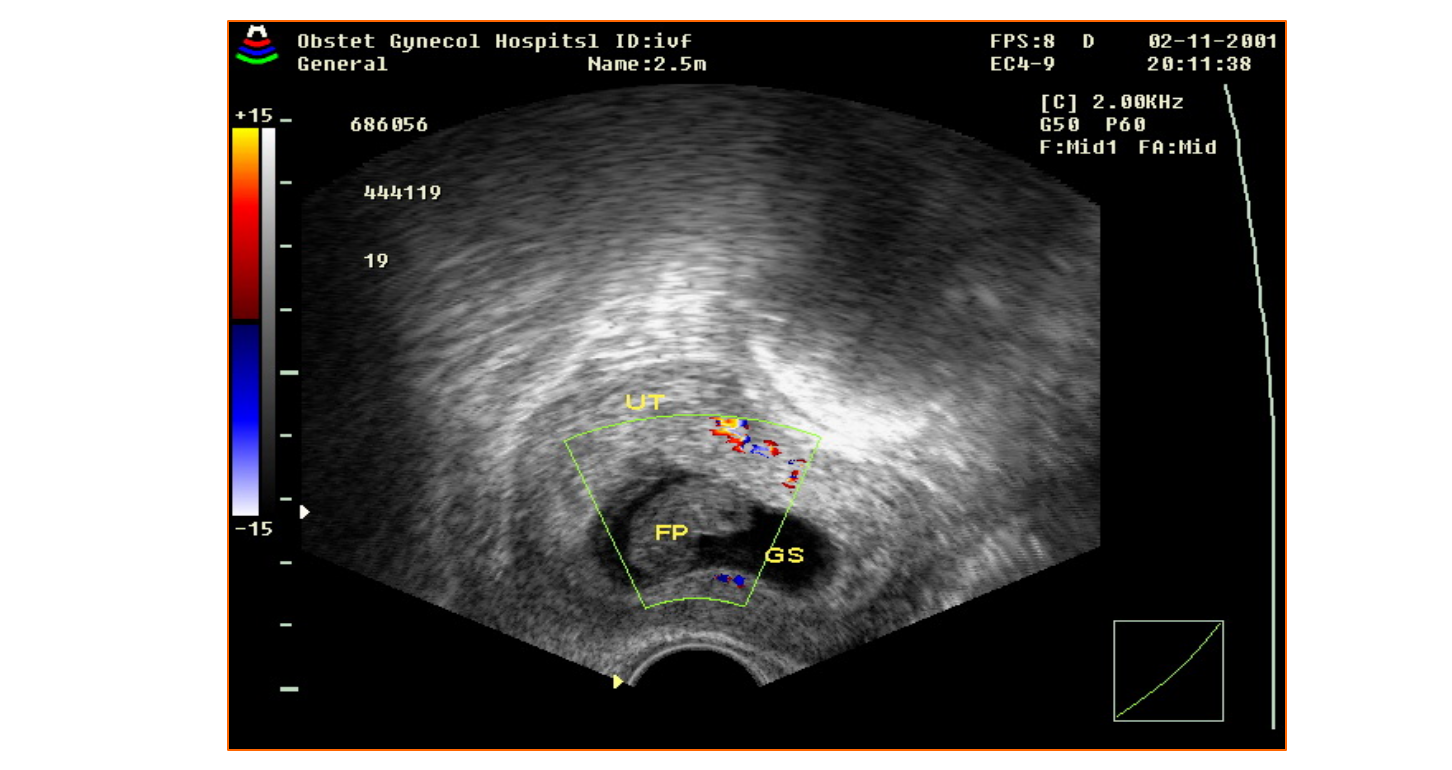

• 4.4 异常妊娠声像图

异常妊娠声像图